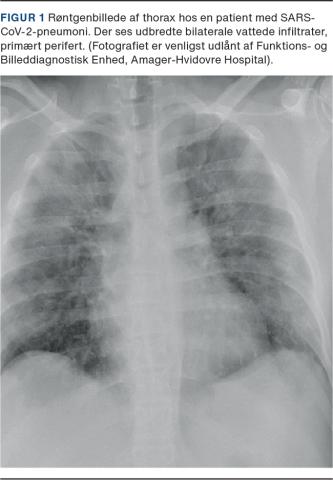

Respiratorisk syncytialvirus

RSV er den hyppigste årsag til pneumoni og bronchiolitis hos børn under fem år [11] og kan blandt voksne med pneumoni påvises i 2-5% af tilfældene [1, 12]. RSV forekommer hyppigst hos patienter over 65 år med underliggende komorbiditet med symptomer såsom hoste, ekspektoration, dyspnø, muskelømhed og feber [13]. 30-70% af patienterne har radiologisk påviste forandringer med infiltrationer, hvoraf unilaterale matglasforandringer og konsolidering er de hyppigste fund Figur 2 [14]. Ældre patienter med komorbiditet er i risiko for at få respirationssvigt, idet en tredjedel får brug for respiratorbehandling, og dødeligheden hos voksne er fundet at være op mod 15% [12].

Billede